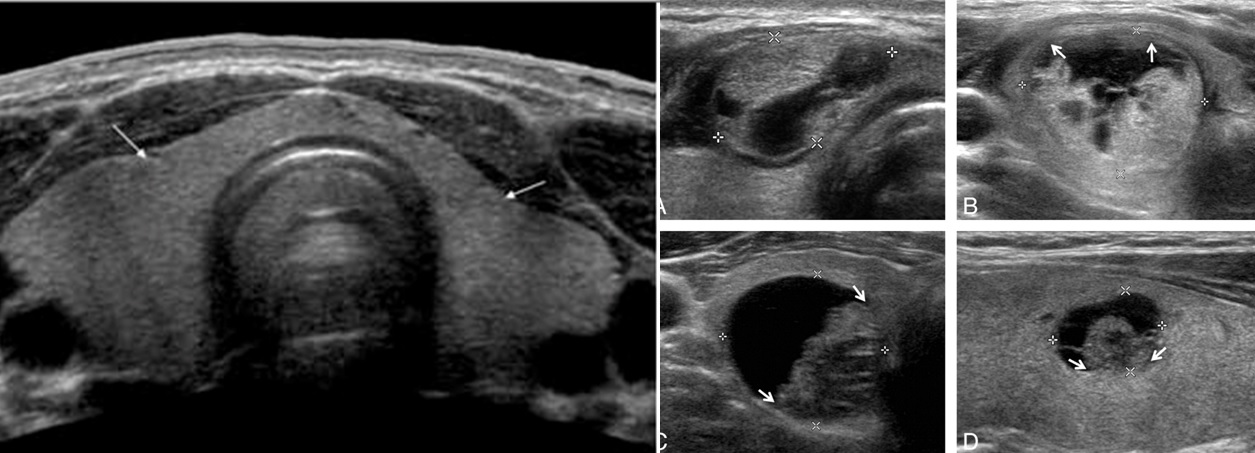

To analyze the appearance of thyroid nodules and determine if they are more likely to be benign, common nodules or have features that may require a biopsy.

If a nodule is detected in the thyroid gland, the radiologist will examine the characteristics of the nodules. Some features suggest that a nodule is benign, while others may indicate that the nodule could be a malignant tumor. In some cases, the radiologist may not be able to make a definite distinction between benign and malignant masses.

In such cases, a thyroid fine-needle biopsy with histopathological evaluation is required. In some cases, a follow-up thyroid ultrasound may be needed 2-3 months later to detect any increase in the size of the nodule.